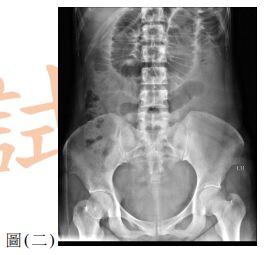

10. 一位60歲女性因腹痛、噁心與嘔吐來急診。此病人有剖腹產與膽囊切除手術病史,其 KUB如圖(二),請問最有可能的診斷為何?

(A) 沾黏性小腸阻塞( adhesive small bowel obstruction ) (B) 大腸阻塞(large bowel obstruction ) (C) 缺血性大腸炎(ischemic colitis) (D) 小腸憩室炎(small bowel diverticulitis)